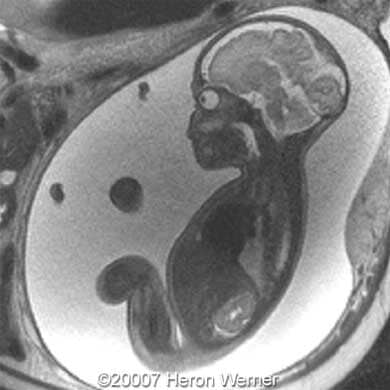

Figures 3, 4: MRI (sagittal T2). Note fluid filled blind ending esophageal pouch.

Figure 7: MRI (coronal T2).